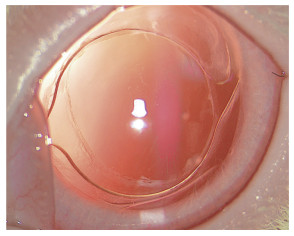

A组术后1 d、7 d、14 d、28 d IOL平均旋转角度无明显变化。B组术后1 d、7 d、14 d随时间延长IOL平均旋转角度增加,术后14 d、28 d IOL平均旋转角度趋于稳定,见图 4。术后1 d、7 d、14 d、28 d A组IOL平均旋转角度小于B组,差异有统计学意义(P < 0.05),见表 3。

| 图 4 B组术后14 d裂隙灯检查浅层巩膜缝线进针点(白色箭头所指)及IOL旋转角度× 16 Fig.4 Superficial sclera suture into the needle point (white arrow point) observed by slit lamp inspection and IOL rotation angle in group B at 28 days after surgery × 16 |

IOL在晶状体囊袋内发生旋转对矫正白内障患者角膜散光的复合曲面IOL影响较大,眼科医师常用IOL旋转角度作为其在囊袋内旋转稳定性的观察指标[17]。本研究结果表明,A组IOL囊袋内旋转稳定性更优越,磨砂化处理后的IOL袢表面粗糙,与囊膜接触摩擦力增大,咬合紧密,有更大的力量抵抗IOL在囊袋内的旋转。B组IOL旋转主要发生在术后早期后囊膜尚无明显混浊机化时,其光滑的袢表面对IOL旋转抵抗力较弱,加之疏水性IOL后表面经过聚乙二醇表面处理后,在一定程度上抵消了IOL材料本身对囊膜的黏附力,使得旋转角度增加;术后14 d、28 d时后囊膜混浊程度逐渐加重,增殖机化的纤维膜填充了囊膜与IOL的间隙,IOL活动空间被压制,因此反而增加了IOL在囊袋内的旋转稳定性。关于兔眼IOL旋转角度如何定位和测量的方法目前少见报道,本研究采用浅层巩膜缝线进针点作为术中IOL袢标记点,直至术后28 d所有兔眼浅层巩膜缝线均未见脱落。